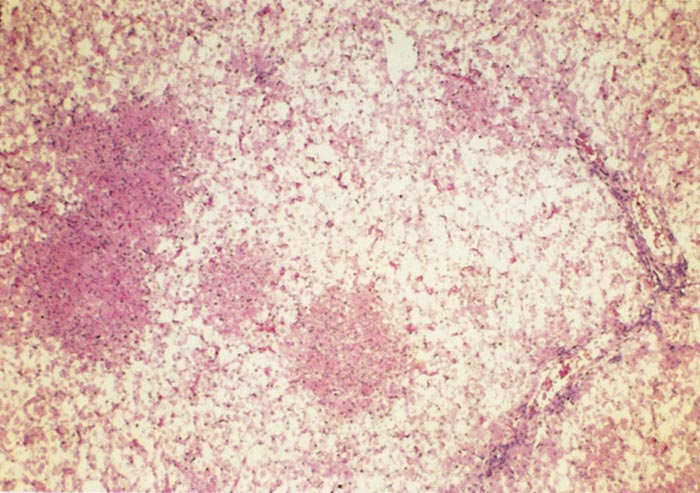

Lesions in target organs such as the liver in the acute disease are produced by the direct lytic effect of the virus on infected cells. In the liver of new-born lambs, for instance, there is initial cloudy swelling and hydropic degeneration of randomly scattered hepatocytes, which soon become necrotic as manifested by acidophilic cytoplasm and pyknotic nuclei. The lesions rapidly progress to form scattered primary necrotic foci of five to eight affected hepatocytes, with the presence of acidophilic cytoplasmic or apoptotic bodies resulting from cytolysis, and infiltration of neutrophils. As the primary lesions enlarge, numerous degenerated and necrotic hepatocytes and acidophilic bodies appear throughout the parenchyma. Ultimately there is massive necrotic hepatitis in which the residual primary foci can still be recognized as dense aggregates of cellular debris infiltrated by leukocytes.117, 168